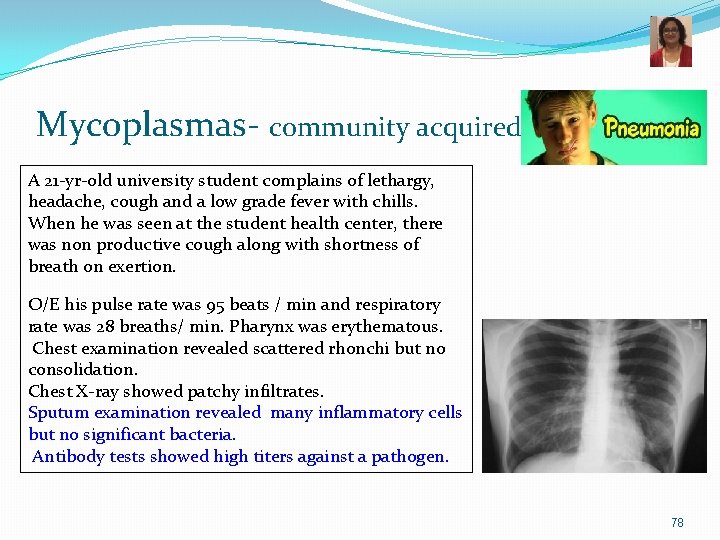

Mycoplasmas- community acquired A 21 -yr-old university student complains of lethargy, headache, cough and a low grade fever with chills. When he was seen at the student health center, there was non productive cough along with shortness of breath on exertion. O/E his pulse rate was 95 beats / min and respiratory rate was 28 breaths/ min. Pharynx was erythematous. Chest examination revealed scattered rhonchi but no consolidation. Chest X-ray showed patchy infiltrates. Sputum examination revealed many inflammatory cells but no significant bacteria. Antibody tests showed high titers against a pathogen. 78